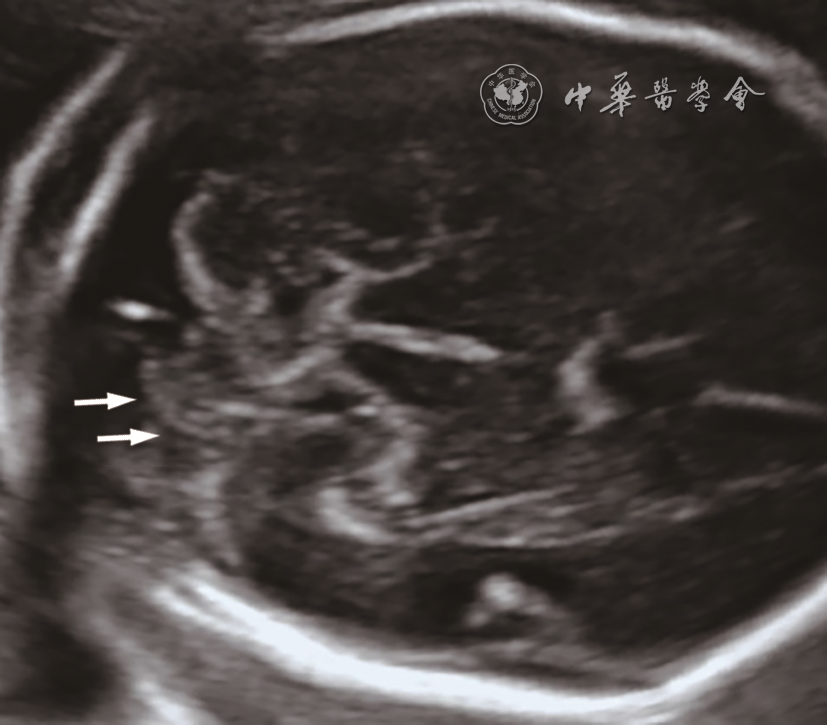

图2 孕22周胎儿(例6)产前颅脑二维超声声像图。小脑横切面声像图示小脑形态失常,右侧小脑半球明显变小;小脑蚓部正常

图3 孕25周胎儿(例5)产前小脑二维超声声像图及产后脑部解剖图。图a小脑横切面声像图示左侧小脑半球明显变小,蚓部显示不清;图b能量多普勒显示左侧小脑半球小而血供较差(箭头所示);图c产后超声声像图示残存的左侧小脑半球实质(箭头所示);图d产后解剖图(颅底观)示左侧小脑下部几乎缺如